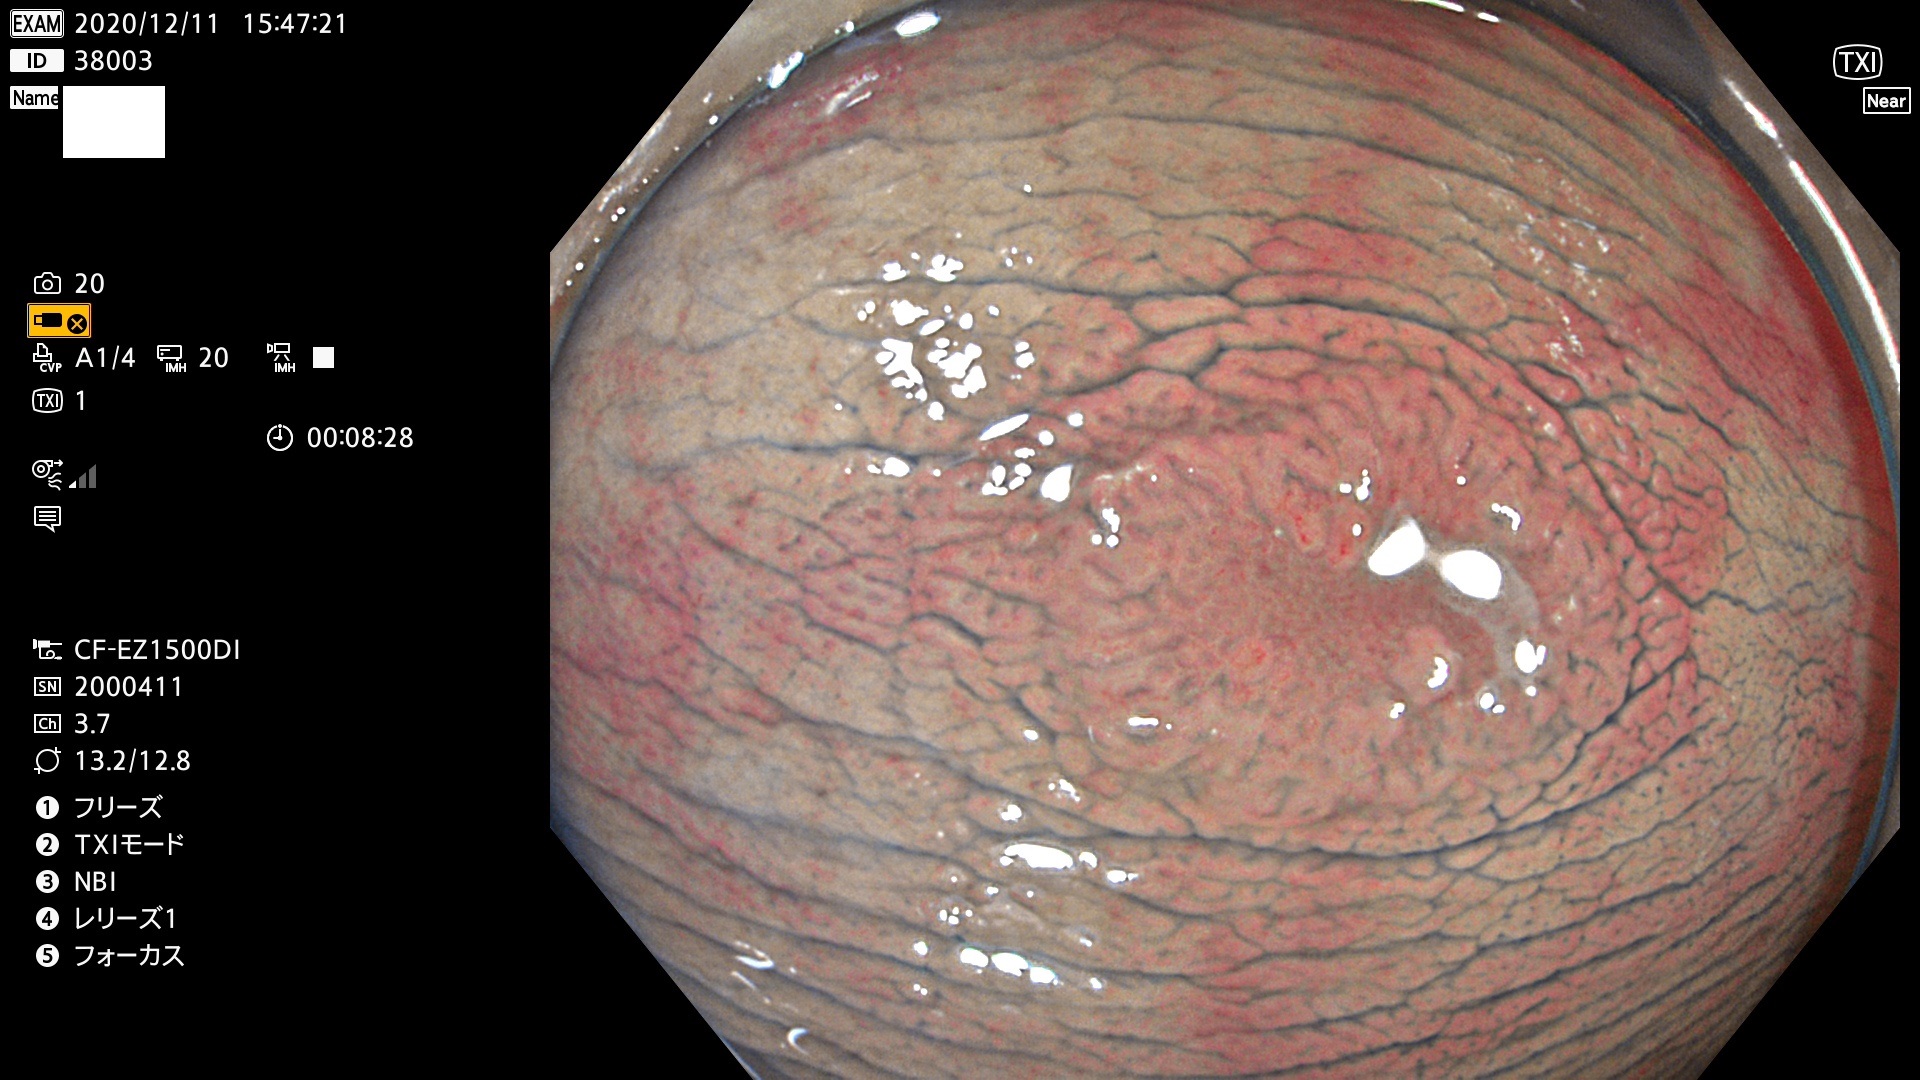

38001 38002 38003 38004 38006(SSAPのみ) 38007 38008 38009 38010 38012 38013 38014 38016 38018 38020 38021 38025 38026 38029 38032 38033 38034 38035 38036 38037(SSAPのみ) 38039 38043 38044 38048 38049 38050 38052 38055 38056 38057 38058 38059 38064(SSAPのみ) 38065 38068 38069 38070 38071 38072 38074 38075 38076 38078 38079 38080 38082 38083 38084 38085(SSAPのみ) 38086 38087 38088 38089 38090 38091 38092 38093 38094 38097 38098 38099

発見困難で危険性の高い平坦型病変(上記100名より抽出)